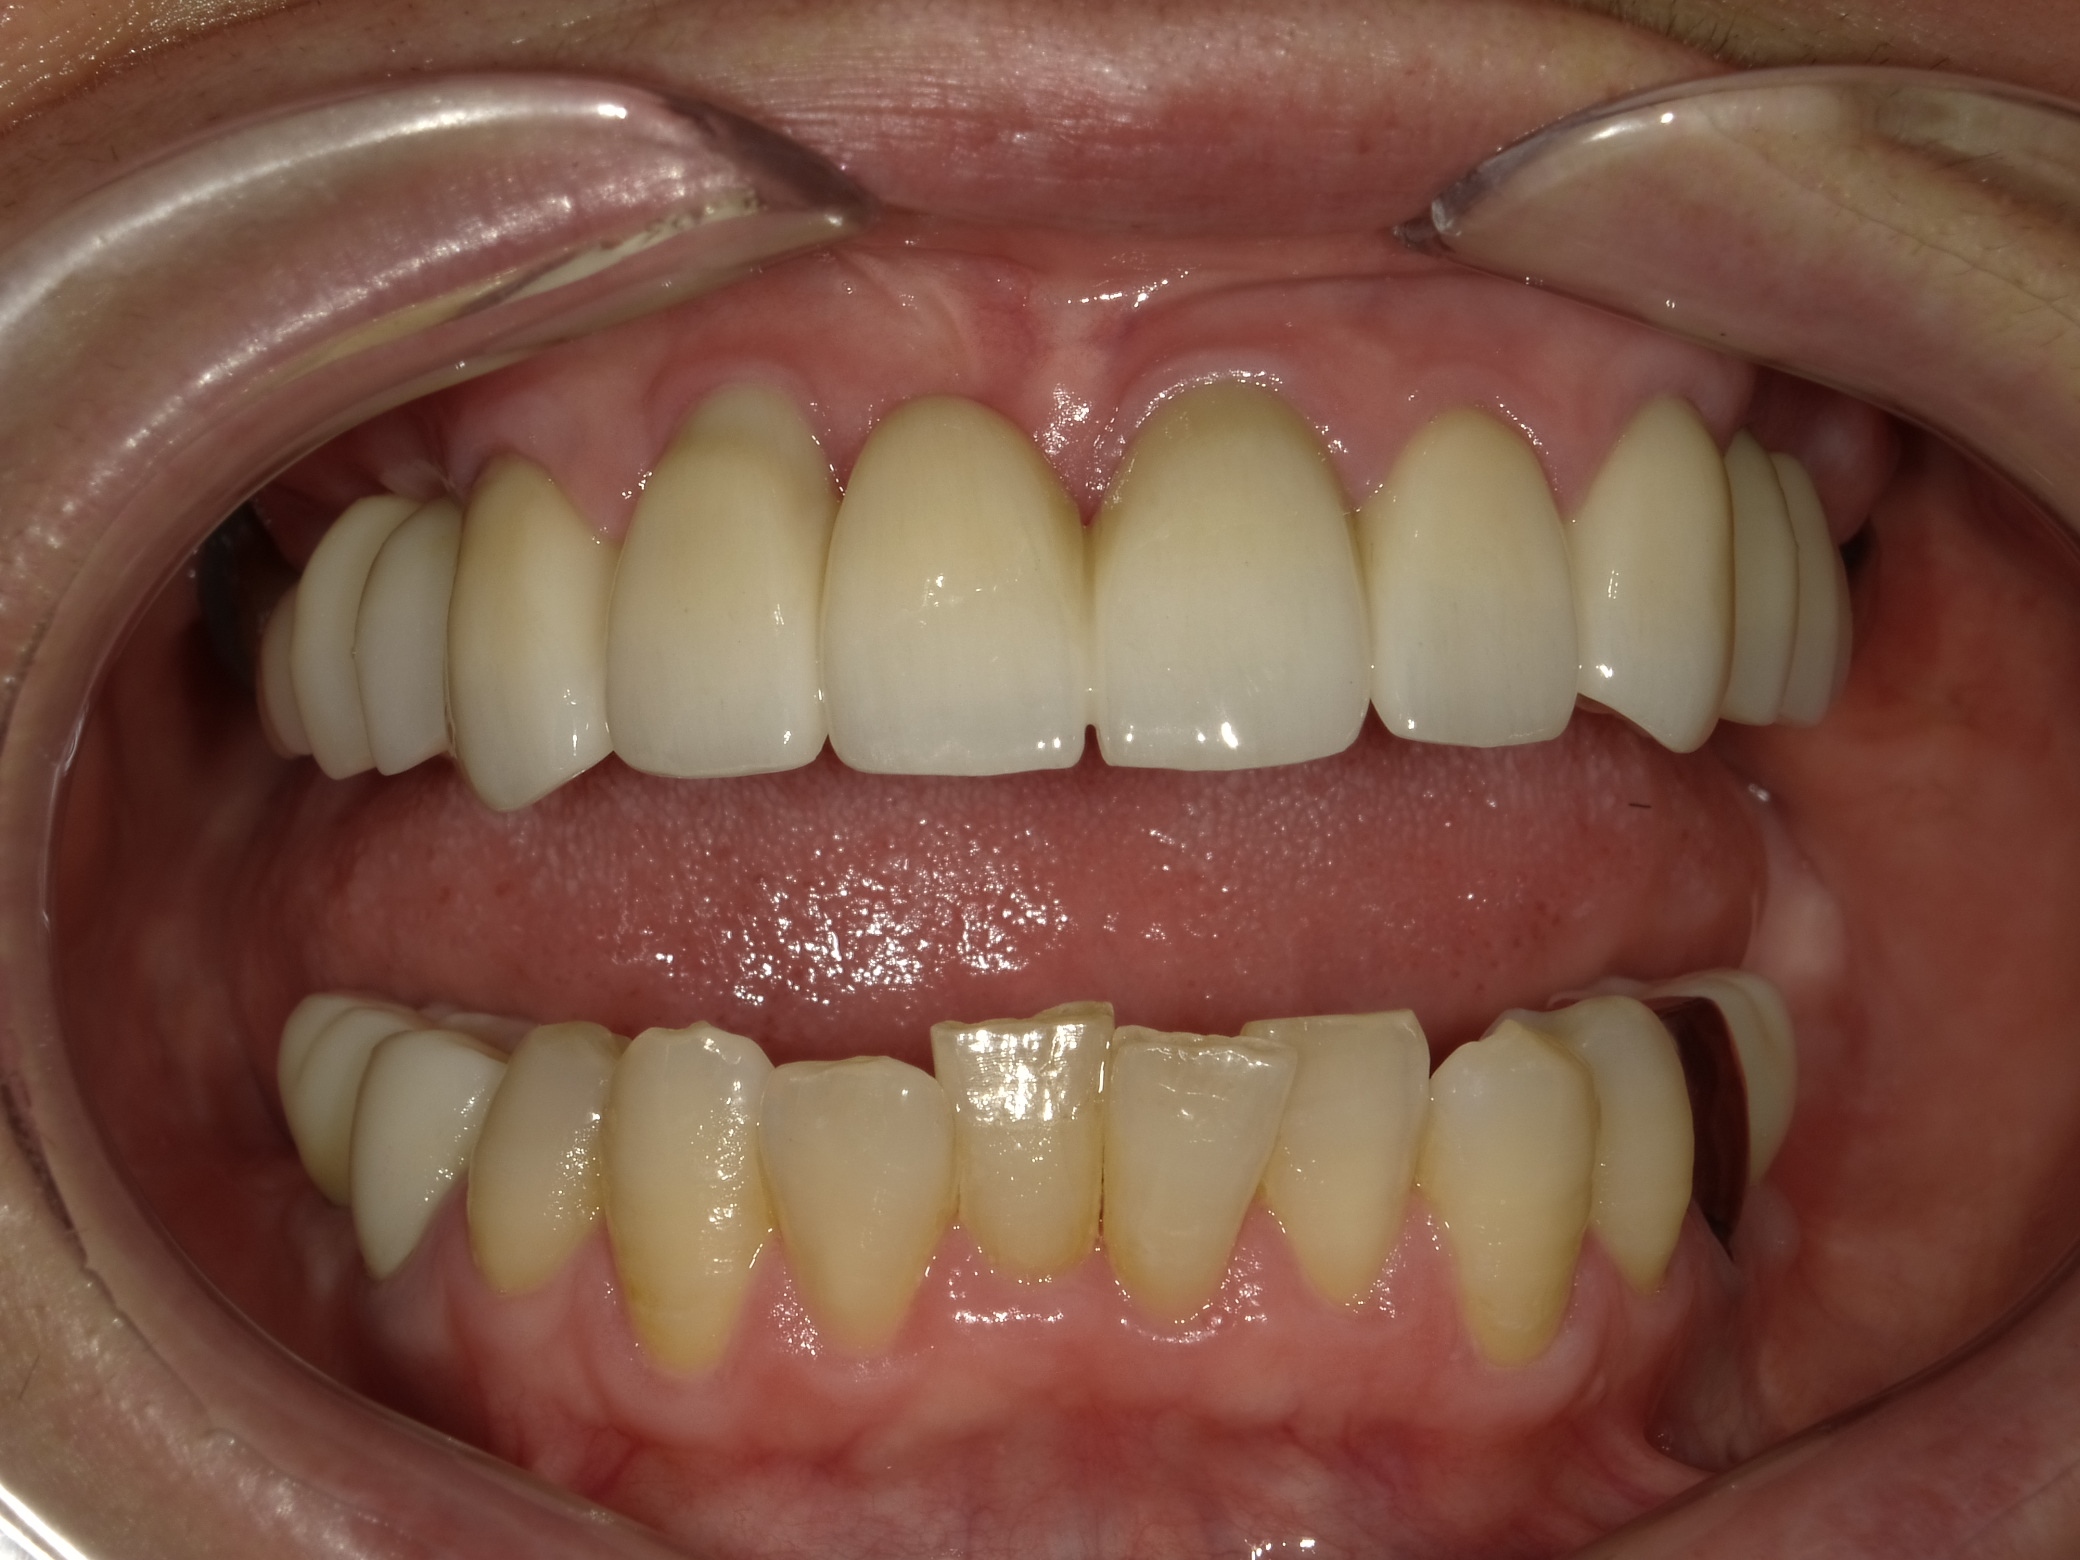

| 主訴 | 全体的に見た目を綺麗にしたい。奥歯でしっかり噛みたい。 |

| 治療内容 | インプラント埋入(右上4・6,左上4・6,右下6,左下6) ジルコニアBr(右上3―左上3) ジルコニア(右下5,左下5) |